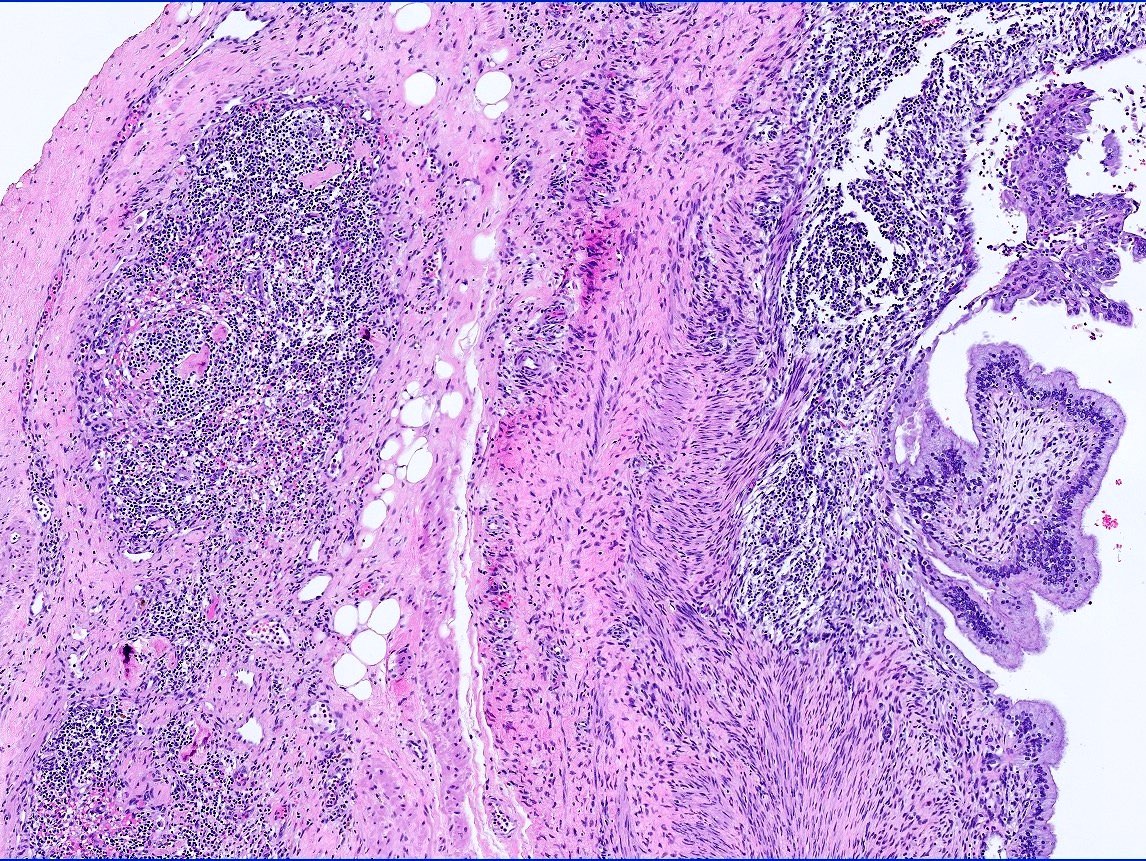

Gross images

Contributed by Debra L. Zynger, M.D.

Microscopic (histologic) images

Testis & epididymis - Staging Board review style question #2

The postpubertal teratoma shown in the gross photo is 1.7 cm and is confined to the testis and did not have lymphovascular invasion. Which is the correct pT category?

Board review style answer #2

A. pT1. Postpubertal germ cell tumors that are confined to the testicular parenchyma and lack lymphovascular invasion are pT1, pT1a or pT1b. Pure seminoma is stratified as pT1a and pT1b based on a 3 cm threshold. Nonpure seminomas are not stratified and therefore this tumor is pT1.

Comment Here Reference:

Testis & epididymis - Staging